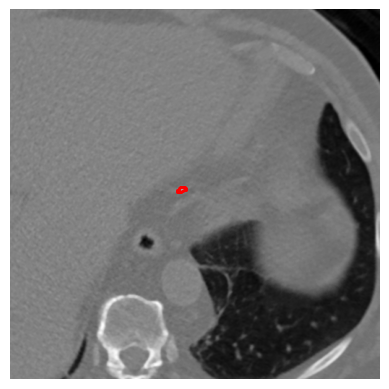

The frequency of label-guided augmentations significantly impacts the model’s focus on regions of interest. In standard DINO training, 8 local crops are generated per image through random cropping. For our label-guided approach, when processing labeled slices (approximately 10% of the dataset), we generate 4 additional guided local crops that specifically target annotated calcified regions. This results in a total of 12 local crops for labeled images (8 random + 4 guided) compared to 8 random crops for unlabeled images. The effective ratio of label-guided crops across the entire training dataset is approximately 5% (0.10×4/120.0330.10\times 4/12\approx 0.033 of all crops), which provides sufficient guidance without overfitting to labeled regions. Figure 3 demonstrates our guided local data augmentation on a CT slice containing calcification, showing examples of the 4 guided local crops extracted from the annotated calcified regions.

Refer to caption

(a) Annotated CT slice with annotation

(b) CT slice without annotation

(c)

(d)

(e)

(f)

(g)

(h)

Figure 3: Representation of guided local data augmentation. Figure aa represents labeled CT slice, while bb represents the same image without annotation. The figures from cc to hh show the guided local data augmentations utilized in DINO training.